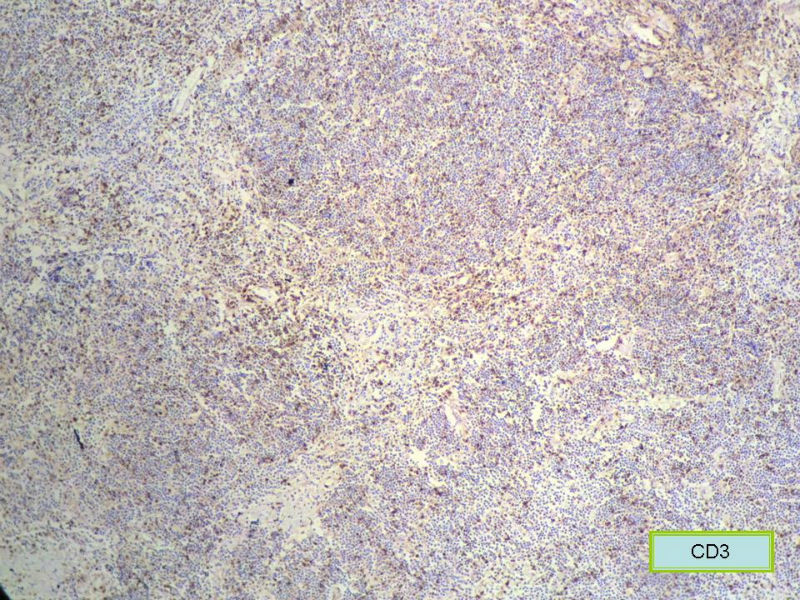

IHC

请再标记CD20和CD79a!图片中阳性不明确,根据T细胞标记看,应该是B细胞结节。Ki67散而少,不支持低级别滤泡性淋巴瘤,若B细胞弥漫阳性,则是惰性B细胞非霍奇金淋巴瘤,首先考虑套细胞,然后是边缘区淋巴瘤。不做生发中心标记,Bcl-2在小B细胞淋巴瘤分类中无意义。

赞成以上专家的讨论,根绝病史,HE形态考虑小细胞病变,CD3、CD5散在+,还是倾向淋巴造血系统病变,CD20、CD79a阳性不明确,可以考虑复查,加做PAX-5,核阳性容易判断,另再加做鉴别其它小细胞肿瘤的抗体:CD99、CD43、CyclinD1、CK、CgA、Syn等,了解病史:骨髓、末梢血、肝、脾等。

上级医院会诊意见:

CD20(+),Kappa(+),ki-67(+)>2%,Lambda(+),Pax-5(+),符合粘膜相关淋巴瘤。